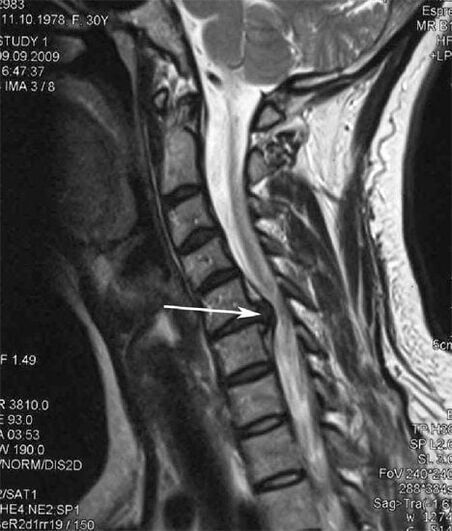

Во почетните фази, остеохондрозата се открива со помош на МНР. Подоцна, патологијата може да се дијагностицира со помош на радиографија. На радиографија на цервикалниот 'рбет, станува забележливо намалување на растојанието помеѓу пршлените, патолошки промени во зглобовите на фасетите и остеофитоза.

Многу луѓе се жалат дека не можат да го свртат вратот поради силната болка што се појавува откако ненадејно подигнале нешто тешко. Овој феномен укажува на формирање на дискус хернија. Причината за болка во грбот, вратот и горниот екстремитет е стискање на еден од нервните корени што излегуваат од 'рбетниот мозок.